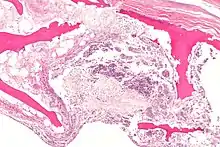

![]() | |

X-ray of hip with femoral head osteonecrosis | |